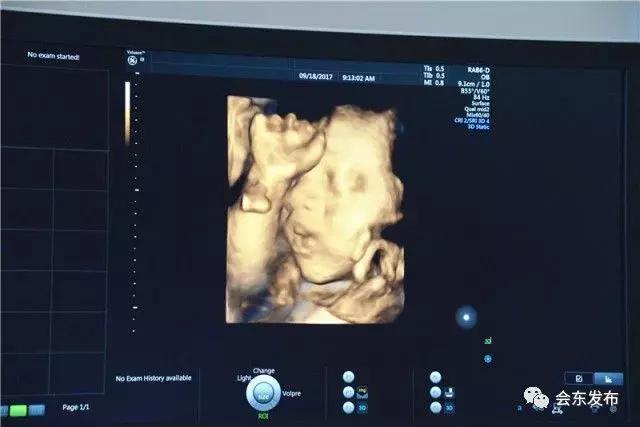

9月21日,会东县妇幼保健计划生育中心引进的美国GE-E8高端四维彩超仪器正式投用。该设备总价值300余万元,填补了会东立体彩色影像诊断的空白,据了解,该设备主要用于产前超声诊断。

“由于需要观察筛检胎儿发育过程*特中**别细小的体征状况,捕捉胎儿最完美的神情姿态,所需的时间相对长一些,因此每天就算仪器运转不停,也只能接待20余位孕妈妈。”富顺保健院前来坐诊的易秋菊专家介绍说,四维彩超不仅可以拍摄极为细致的立体、连动的影像,而且能对胎儿发育状况进行评价,为各种先天性疾病提供准确全面的科学依据,使其得到最好的诊治。

据了解,四维彩超是目前世界上最先进的彩色超声设备,虽存在射线、光波和电磁波等方面的辐射,但对人体的健康没有影响。四维彩超能够多方位、多角度观察宫内胎儿的生长发育情况,在优生优育方面起着非常重要的作用;能进行宫内写真,为宝宝留下永久纪念,成为准妈妈们必不可少的检查项目。